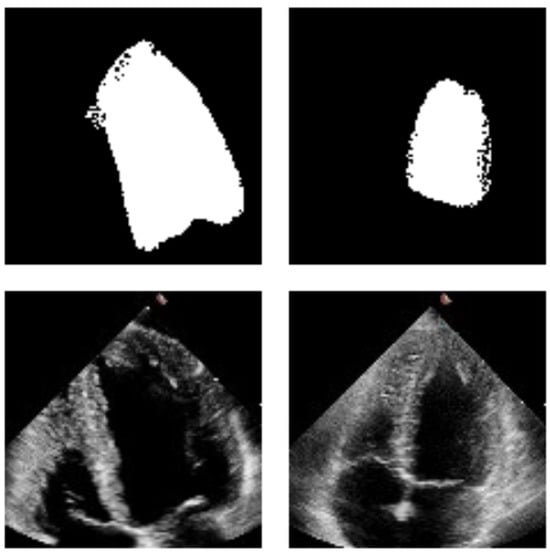

4.2. Qualitative Analysis

3.5.1. Visual Inspection of Segmentation Results